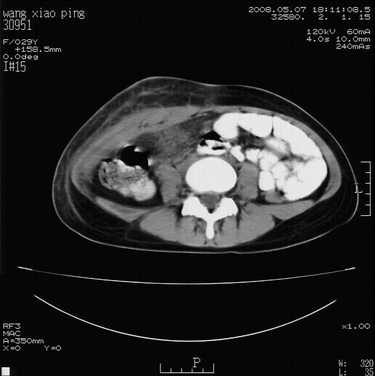

标题: CT13306:F,29,阑尾炎手术后20天,右下腹切口处包块. [打印本页]

标题: CT13306:F,29,阑尾炎手术后20天,右下腹切口处包块.

b超切口疝。

皮肤切口愈合良好。炎性肿块?

肿块密度较低,周围见有条索状影,边界不清,考虑为炎性病变可能大,必要是做增强看看。

支持阑尾术后切口感染。

切口处见液性密度影,周围肌肉肿胀,脂肪层密度增高。

符合术后并发症。